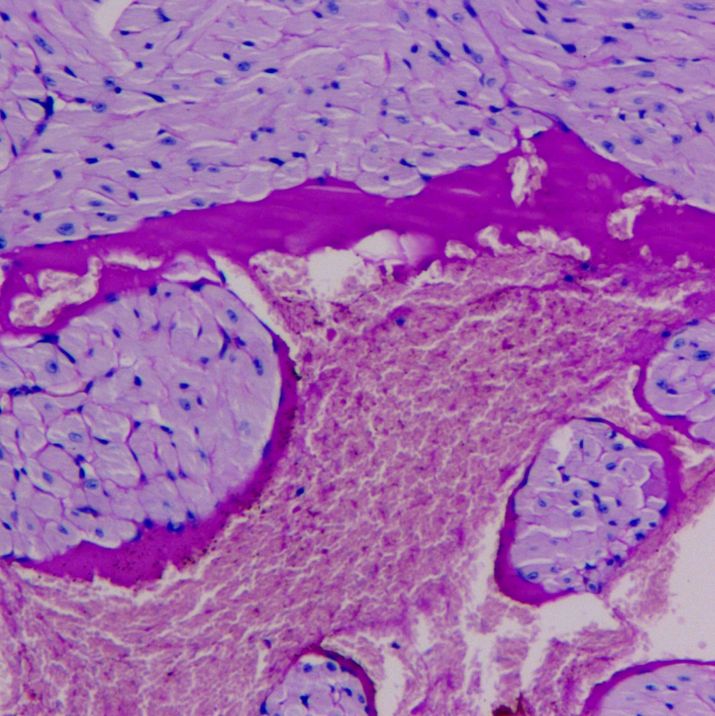

文献和实验PAS染色原理

细胞胞浆中存在糖原或多糖类物质(如糖蛋白、粘多糖、糖脂、粘蛋白等),过典酸能使细胞内的多糖乙二醇基氧化为二醛基,其与Schiff试剂中的无色品红结合后呈现紫红色,沉积在细胞内多糖所在之处。

糠秕孢子菌毛囊炎是由圆形或卵圆形糠秕孢子菌引起的毛囊炎改变,其皮损特征表现为圆顶状毛囊性丘疹或脓皰样损害。 临床表现 1.青壮年多见; 2.皮损好发于胸背和上臂; 3.皮损表现为圆顶状毛囊性丘疹或脓皰样损害,直径2-4mm,按痤疮治疗无效。 诊断依据 1.皮损好发于胸背、上臂; 2.典型皮损表现; 3.皮屑直接镜检可见短杆状菌丝及圆形孢子; 4.皮损组织病理(PAS染色)毛囊内可见大量圆形或卵圆形芽生孢子。 治疗